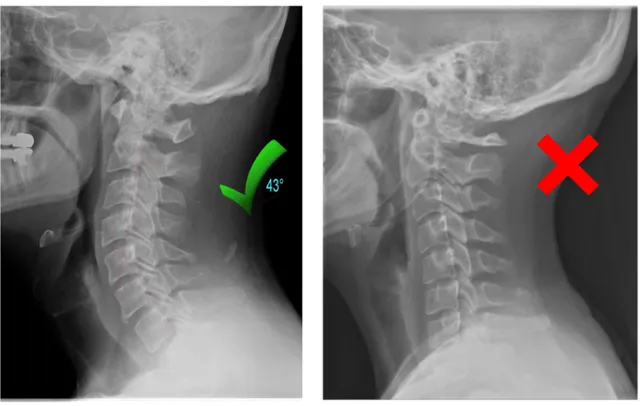

✓ Restoring the natural curve in your neck